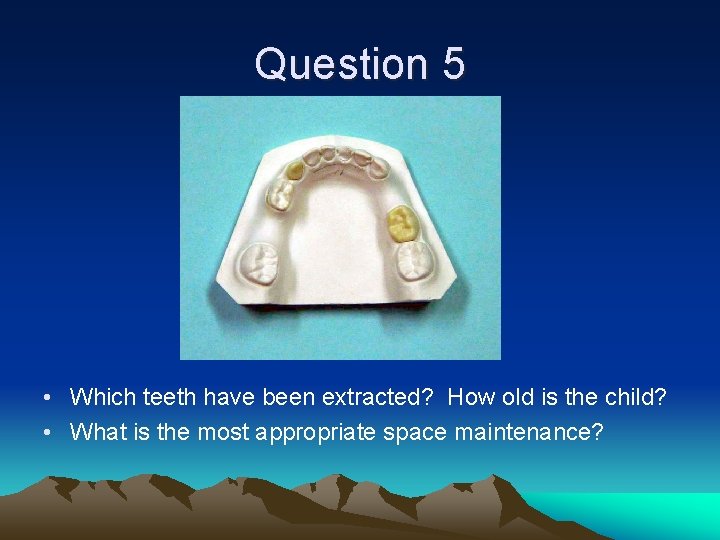

Question 5 • Which teeth have been extracted? How old is the child? • What is the most appropriate space maintenance?

Question 5 • Teeth #K and #S extracted. 5 -6 y. o. child. • Because permanent incisors are not erupted, LLHA not recommended. Options: Reverse band loop #L-#19 and band loop #T-#R.